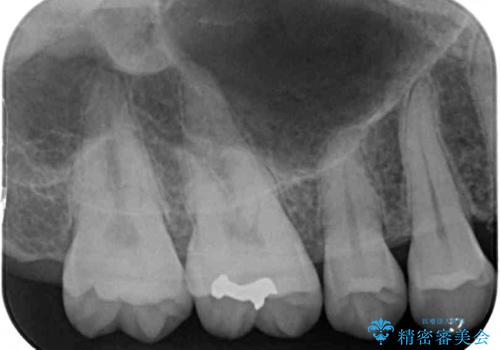

- 奥歯の銀歯と虫歯を気にして来院された患者様です。

下顎は口を開けたときに目立つためセラミックインレーに、上顎奥歯は機能面を優先してゴールドインレーにて修復治療を行うこととしました。

機能面を優先すると、PGAインレー(ゴールドインレー)による修復治療やPGAクラウンによる補綴治療が望ましいのですが、笑ったときに見えている銀歯がどうしても気なってしまうとのことで、目立ってしまう奥歯はセラミックインレーやセラミッククラウンを装着することとしました。